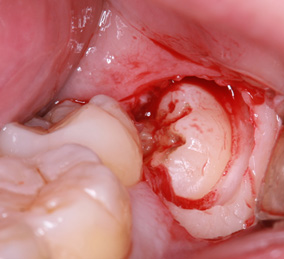

親知らずの歯根の先端と下顎神経が近接している場合は2回に分けて抜歯を行うことがあります。まず、親知らずを2分割して頭の部分を抜きます。その後しばらく期間をおいて、のこる歯根の部分が頭を抜いたスペースに移動したのを確認して抜きます。

このように2回に分ける事で安全な抜歯が可能です。

当院で処置した2回法による親知らずの抜歯について詳細を下記よりご覧いただけます。

※歯肉の切開、出血を伴う写真がございます。

2回法親知らずの抜歯処置を表示する

まず歯冠を切除し、疼痛がでないよう、冠部歯髄を除去してネオダイン(歯髄の鎮痛鎮静、象牙質の消毒、覆髄)を填入します。その後、粘膜骨膜弁にて完全閉鎖を行います。以下に処置の流れを示します。